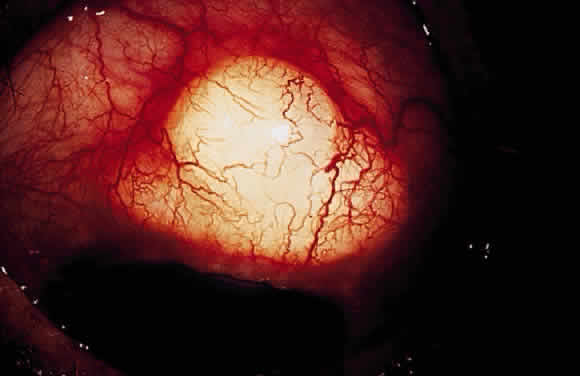

Hypotony Maculopathy

Some patients with intraocular hypotony develop loss of central vision secondary to marked irregular folding of the choroid and retina. Initially, these folds are broad and not sharply delineated. They tend to radiate outward in a branching fashion temporally from the optic disc and concentrically or irregularly nasally to the disc. There may be swelling of the peripapillary choroid simulating papilledema (Fig. 3). The retina often shows a series of stellate folds around the center of the fovea. The retinal vessels are tortuous and sometimes engorged. The primary cause of visual loss is the marked folding of the central retina. Early detection of this condition is important because correction of the cause usually results in visual improvement. In cases of prolonged hypotony, permanent pigmented lines, caused by changes in the retinal pigment epithelium, occur in the macular area and nasally. A postoperative bleb leak and a cyclodialysis cleft were formerly the most common causes of hypotony maculopathy. The incidence of hypotony maculopathy after glaucoma surgery has increased with the use of antifibrotic agents, specifically mitomycin C. A direct toxic of mitomycin cannot be ruled out. The maculopathy is most likely to occur in young myopic patients, who may have a sclera more susceptible to swelling and contraction.11–14